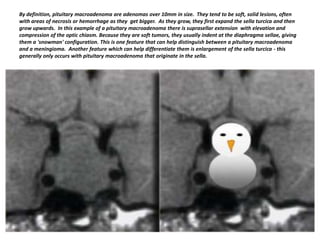

By definition, pituitary macroadenoma are adenomas over 10mm in size. They tend to be soft, solid lesions, often

with areas of necrosis or hemorrhage as they get bigger. As they grow, they first expand the sella turcica and then

grow upwards. In this example of a pituitary macroadenoma there is suprasellar extension with elevation and

compression of the optic chiasm. Because they are soft tumors, they usually indent at the diaphragma sellae, giving

them a 'snowman' configuration. This is one feature that can help distinguish between a pituitary macroadenoma

and a meningioma. Another feature which can help differentiate them is enlargement of the sella turcica - this

generally only occurs with pituitary macroadenoma that originate in the sella.